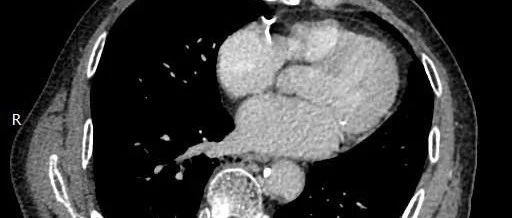

老年男性,肺癌!

一医学影像        yxyx-app  医学影像APP,打造伴随医生快速成长的影像学习社区。与影像园(Xctmr.com)一起提供最全面的影像案例库、基础(解剖、病理、影像诊断)知识、影像技术及考题等,为医生提供最佳的医学影像参考。经典病例【所属科室】肿瘤科【基本资料】患者,男,74岁【主诉】发现左下肺癌半个月...